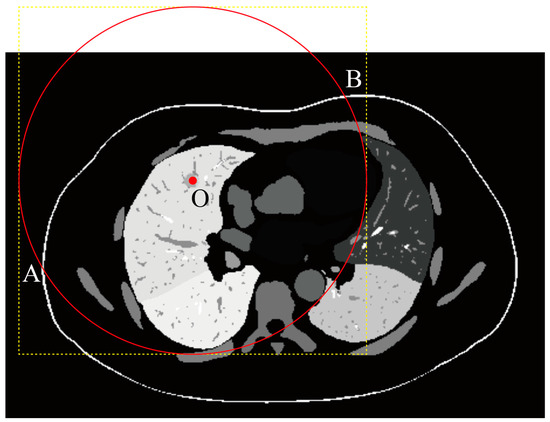

2.3.2. Biopsy Needle Length Constraint

- 1.

- The tail is outside the skin: .

- 2.

- The line segment from the tail to intersects the skin surface .

- 3.

- The tail position is within the visible skin region of the CT scan.

2.4.3. ROI Cropping